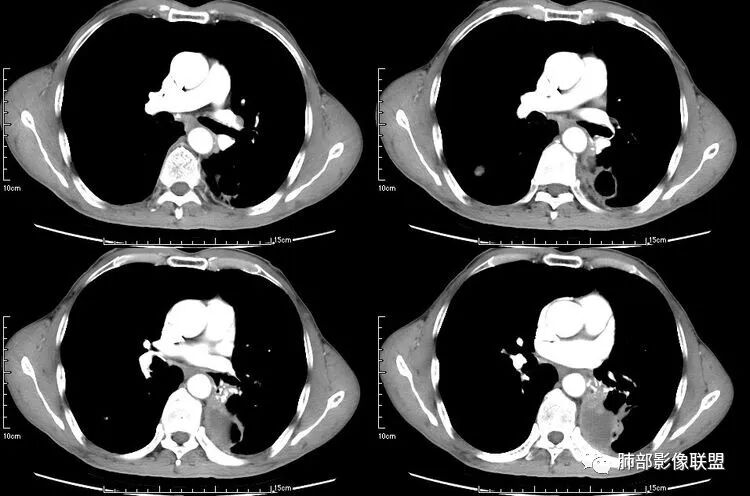

患者老年男性,咳嗽、咳痰、痰中带血伴胸闷2月余。长期大量吸烟史。查肝肾功能、血糖、血脂、心肌酶、电解质、血沉、C反应蛋白、抗“O”、类风湿因子、抗核抗体谱无明显异常。肿瘤标志物提示NSE、CYFRA21-1稍升高。胸部CT:肺气肿背景,左肺下叶后基底段不规则肿块影,见支气管截断,内见大片状低密度区及部分血管影,增强轻度强化,远端空洞形成。双肺多发不规则实性结节影、见毛刺、胸膜牵拉及血管集束,结节内见空洞形成,部分可见血管影,多位于胸膜下。双肺见多发肺大泡。综合考虑左下肺恶性病变并双肺转移。鳞癌或淋巴瘤可能。鉴别血管炎性病变及真菌感染。

本病例左肺下叶肿块,有深分叶、毛刺、胸膜牵拉凹陷、支气管截断及纵隔内淋巴结肿大等征象,都均支持病灶为恶性,如腺癌,而且叶间裂的多发结节也提示是腺癌来源可能大;双肺多发结节、肿块,大部分病灶有分叶、毛刺及胸膜凹陷的恶性征象,与原发肿瘤本身的性质有关,所以应该与左肺下叶肿块同源,而且双肺多发病灶内空洞也具有多样性;

此病例中空洞形态多样,内壁不光整,有分隔影,周围未见明显卫星灶及钙化灶,结核不太符合;患者病史慢性病史,无明显发热,缺乏中毒临床表现,急性感染基本排除;各种中性粒细胞胞浆抗体阴性,没有鼻窦炎,肾脏等病史,基本排除血管炎;霉菌性空洞常见于免疫机能低下者, 常为空洞、肺炎、伴“ 晕圈”征的结节及支气管扩张合并存在。